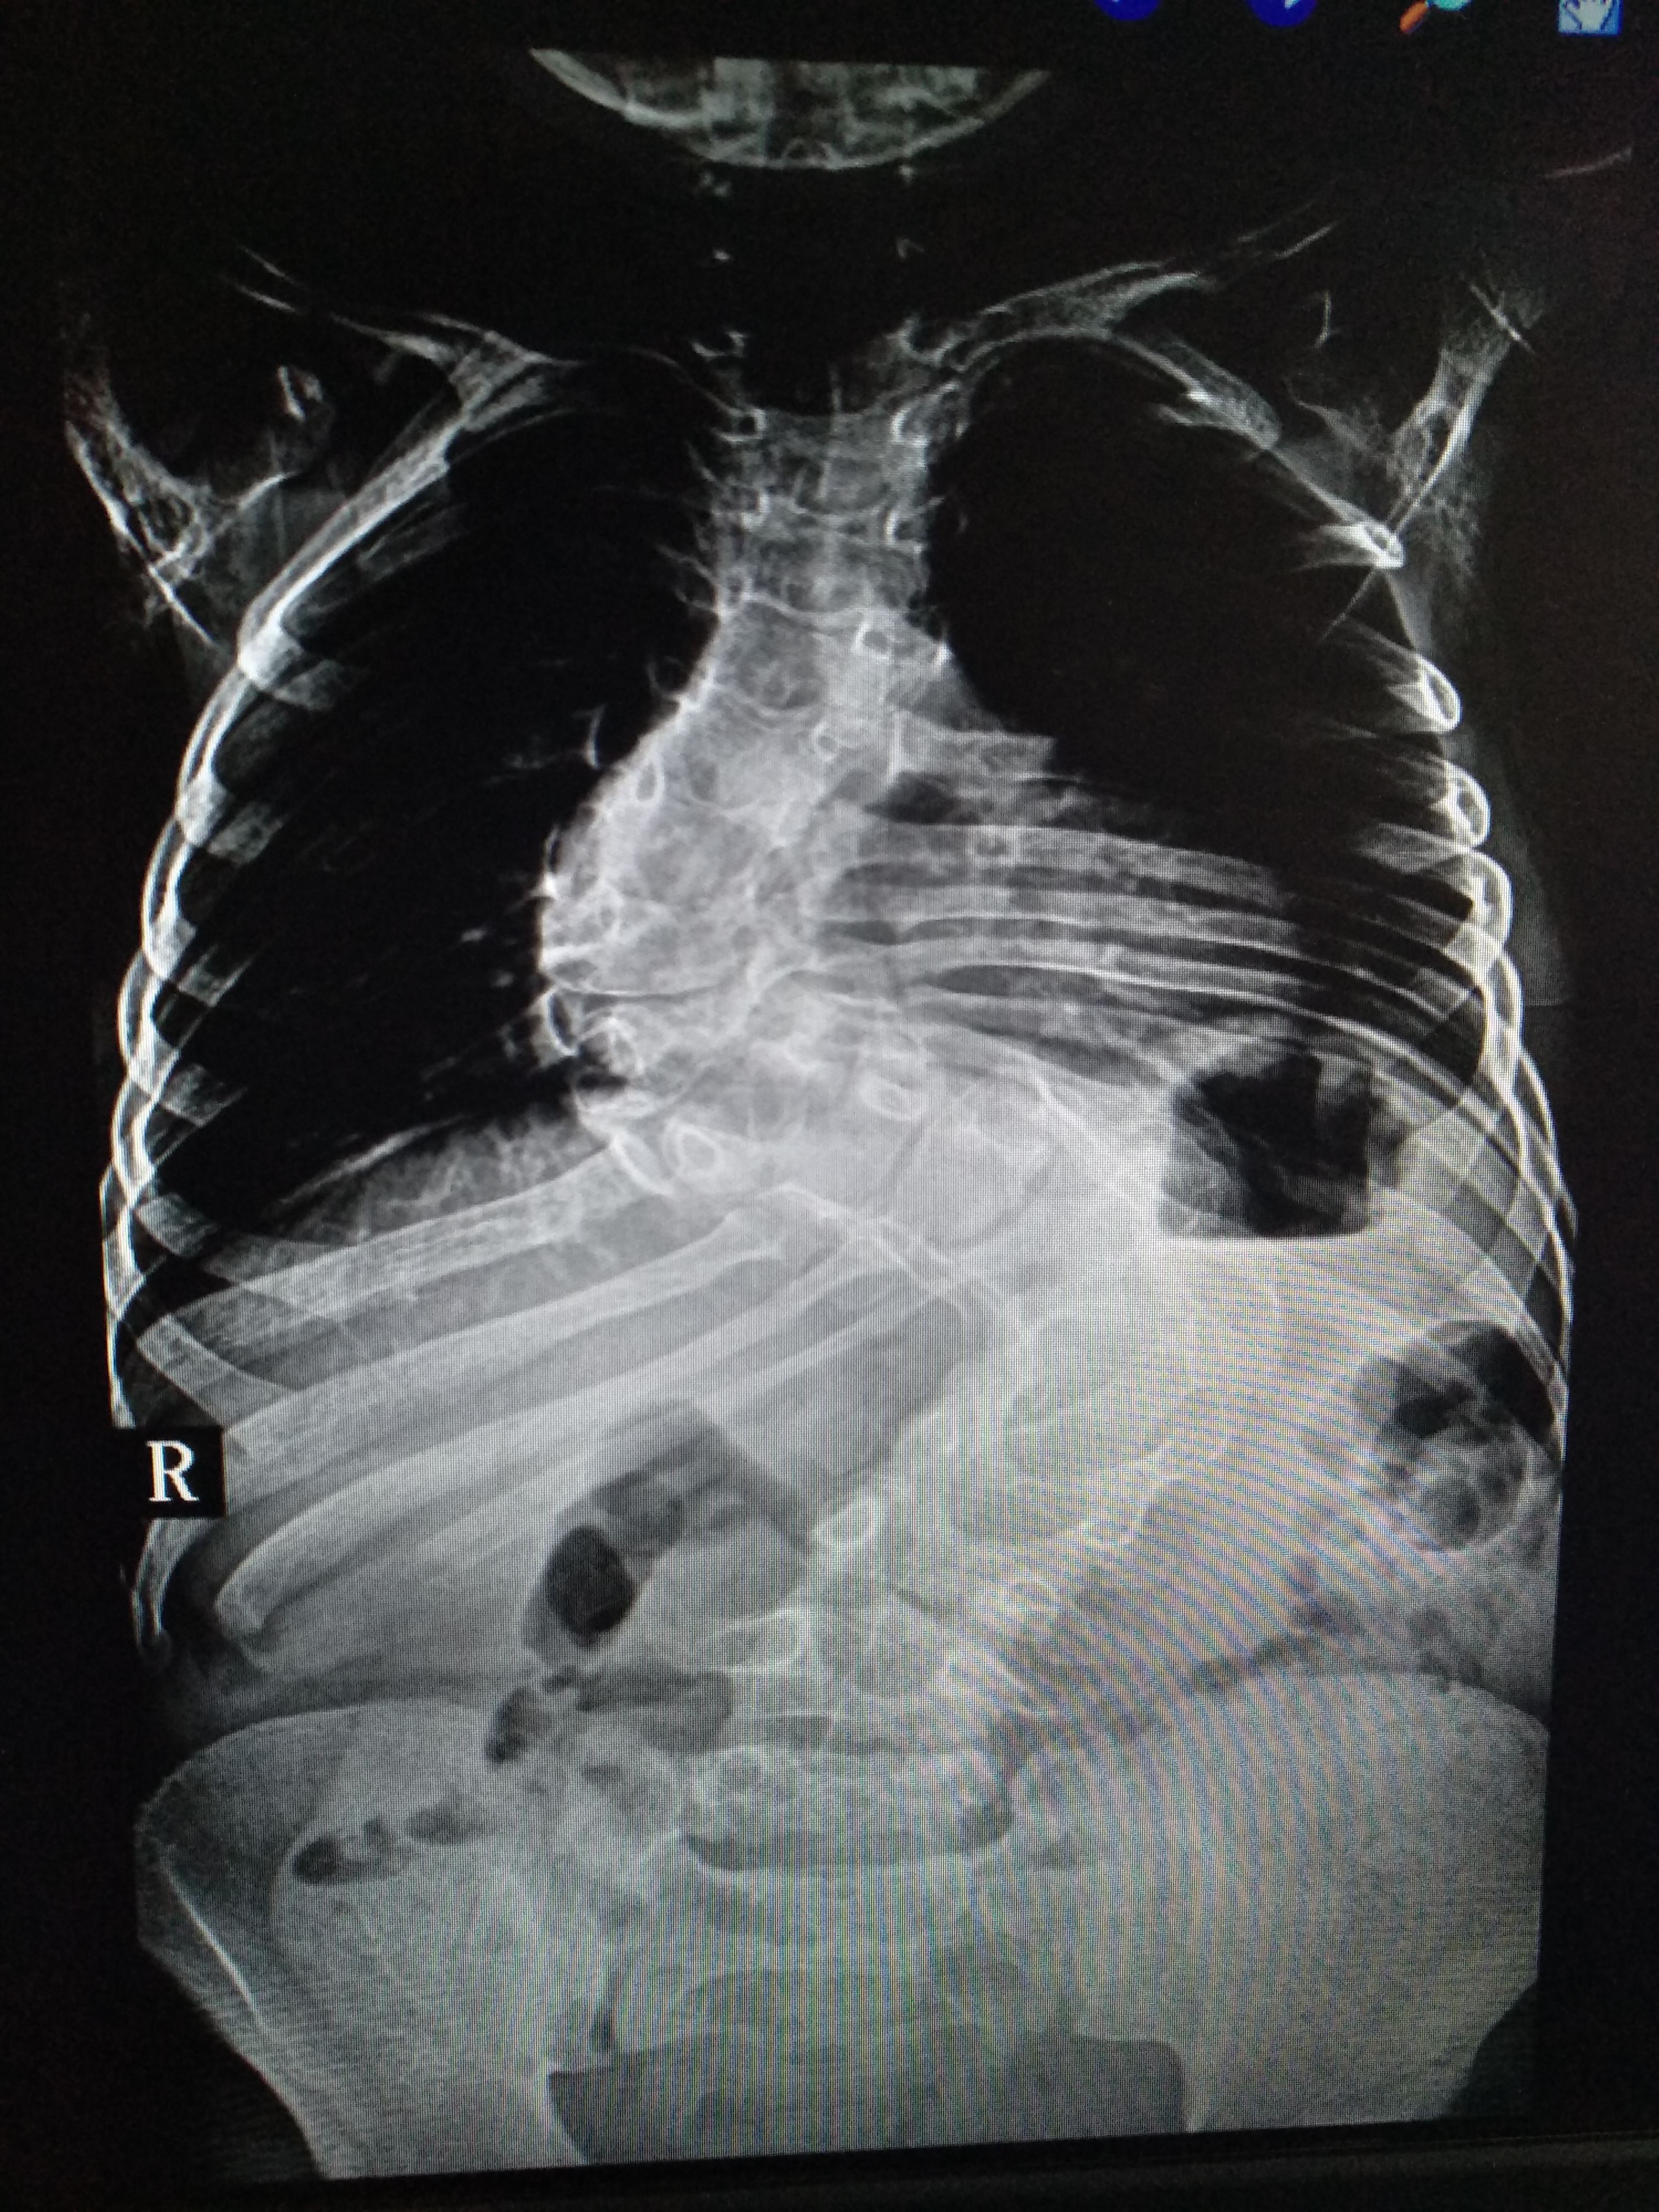

在索县的门诊工作中,田医生遇到一位10岁的藏族姑娘,她从小患有脊柱侧弯,虽然已经11岁了,但身高仅105 cm。严重的脊柱畸形不但对小姑娘的心肺功能造成非常严重的影响,而且给孩子和家长都造成巨大的心理负担。小姑娘家境一贫如洗,加上弟弟也患有下肢疾病,家里的收入仅能支付一家四口吃饭和两孩子上学。田医生在仔细询问病史和详细查体后对小姑娘的病情进行了全面评估,建议小姑娘到北京解放军306医院进行分期矫形手术治疗。田医生向医院领导和索县相关部门的领导汇报了这个病例,306医院的领导已经同意为小姑娘进行手术治疗并减免医疗费用,希望出身贫寒的她可以从此"站立起来"!孩子的母亲得知这一消息后喜极而泣,给解放军306医院的专家们行跪拜礼,用藏语念叨着:*产党共**好!解放军好!

藏族小姑娘患有严重的脊柱侧弯,即将赴京接受一期手术治疗